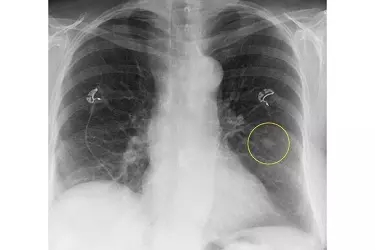

An x-ray is a noninvasive medical test that helps physicians diagnose and treat medical conditions. Imaging with x-rays involves exposing a part of the body to a small dose of radiation to produce pictures of the inside of the body.

X-rays are the oldest and most frequently used form of medical imaging. X-Rays give a lot of information about the bones within the body but the advances in X-Ray technology over the years have made it a good diagnostic tool even for soft tissue information.

The advantages of a digital radiography are many. The image procured in the digital format can be seen by the radiologist in a much better way by zooming on any part of the image. The images can be moved in 360 degree direction which helps in correct diagnosis of the problem.

Digital images of the xray are evaluated by a radiologist who makes the report. The digital images of the xray can also be sent to your treating doctor who can also interpret the images to make the diagnosis.